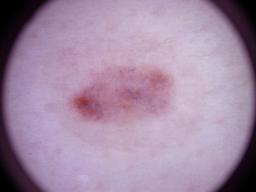

Melanoma and Nevus Dermoscopy Images with Confirmed Histopathological Diagnosis

- Name: Melanoma and Nevus Dermoscopy Images with Confirmed Histopathological Diagnosis

Description:

Collection defined by Dr. Jorge A. Rios-Duarte for a research project.